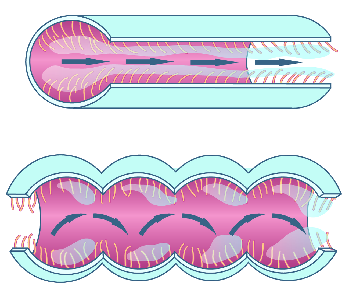

Detailreiche Fotografien aus der medizinischen Praxis ergänzen die Texte; moderne, genaue,

wissenschaftliche Zeichnungen geben Einblick in die Anatomie und die Funktion der Lunge und

anderer Organe.